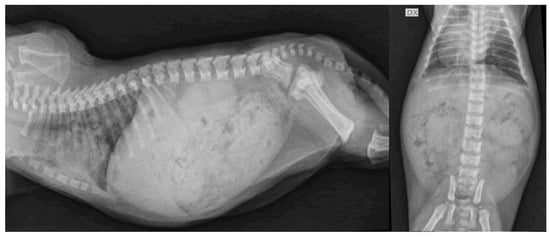

4. Clinical Cases

4.1. Case Description